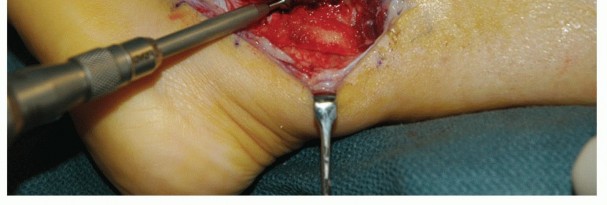

| Carry the incision down to the level of the peroneal tendon sheath (TECH FIG 1A). | |||

TECH FIG 1 • A. Intraoperative photograph of a left ankle (lateral approach) shows the peroneal tendons subluxing anteriorly (brevis is the gray arrowhead , longus is the white arrowhead , SPR is the black arrow). B. The peroneal tendons have been retracted anteriorly by the Penrose drain. Elevation of an anterior-based periosteal flap (outlined by dots) from the fibular groove has been completed. The black arrow shows the remnant of the SPR posteriorly. C. The tendons are relocated, after a groove-deepening procedure, into the recreated groove. The white dots outline the anteriorly based periosteal flap. It is then brought over to the posterior remnant of the SPR (black arrow). D. The flap is sutured to the remnant SPR with nonabsorbable sutures, completing the superior peroneal retinaculoplasty. |

| Inspect the SPR. Usually, it is attenuated and deficient, especially along its anterior border. The retinaculum often is lifted off its fibular attachment, thus allowing the peroneal tendons to subluxate. | |||

| Make an incision in the peroneal sheath along the posterior border of the fibula. Retract the peroneal tendons anteriorly (TECH FIG 1B). | |||

| We routinely reinforce the SPR with a soft tissue periosteal flap elevated from the fibular groove from a posterior to anterior direction. | |||

| Raise the periosteal flap, measuring about 1.0 × 3.0 cm, sharply, from posterior to anterior. After the flap is | |||

| raised, a groove-deepening procedure may be performed when indicated. | |||

| Use a burr to deepen the groove 6 to 9 mm with all raw bony edges. The groove should extend from the fibular tip to 5 cm proximal. We use bone wax to smooth the groove. | |||

| Reduce the peroneal tendons and use the periosteal flap to contain the tendons, with the visceral side of the periosteum facing the tendons (TECH FIG 1C). | |||

| Suture the flap to the posterior remnant of the SPR with a series of 3-0 polybraided nonabsorbable sutures (TECH FIG 1D). | |||

| Range the ankle to evaluate the soft tissue repair, being sure that the tendons are free to move within the reconstructed peroneal tendon sheath. | |||